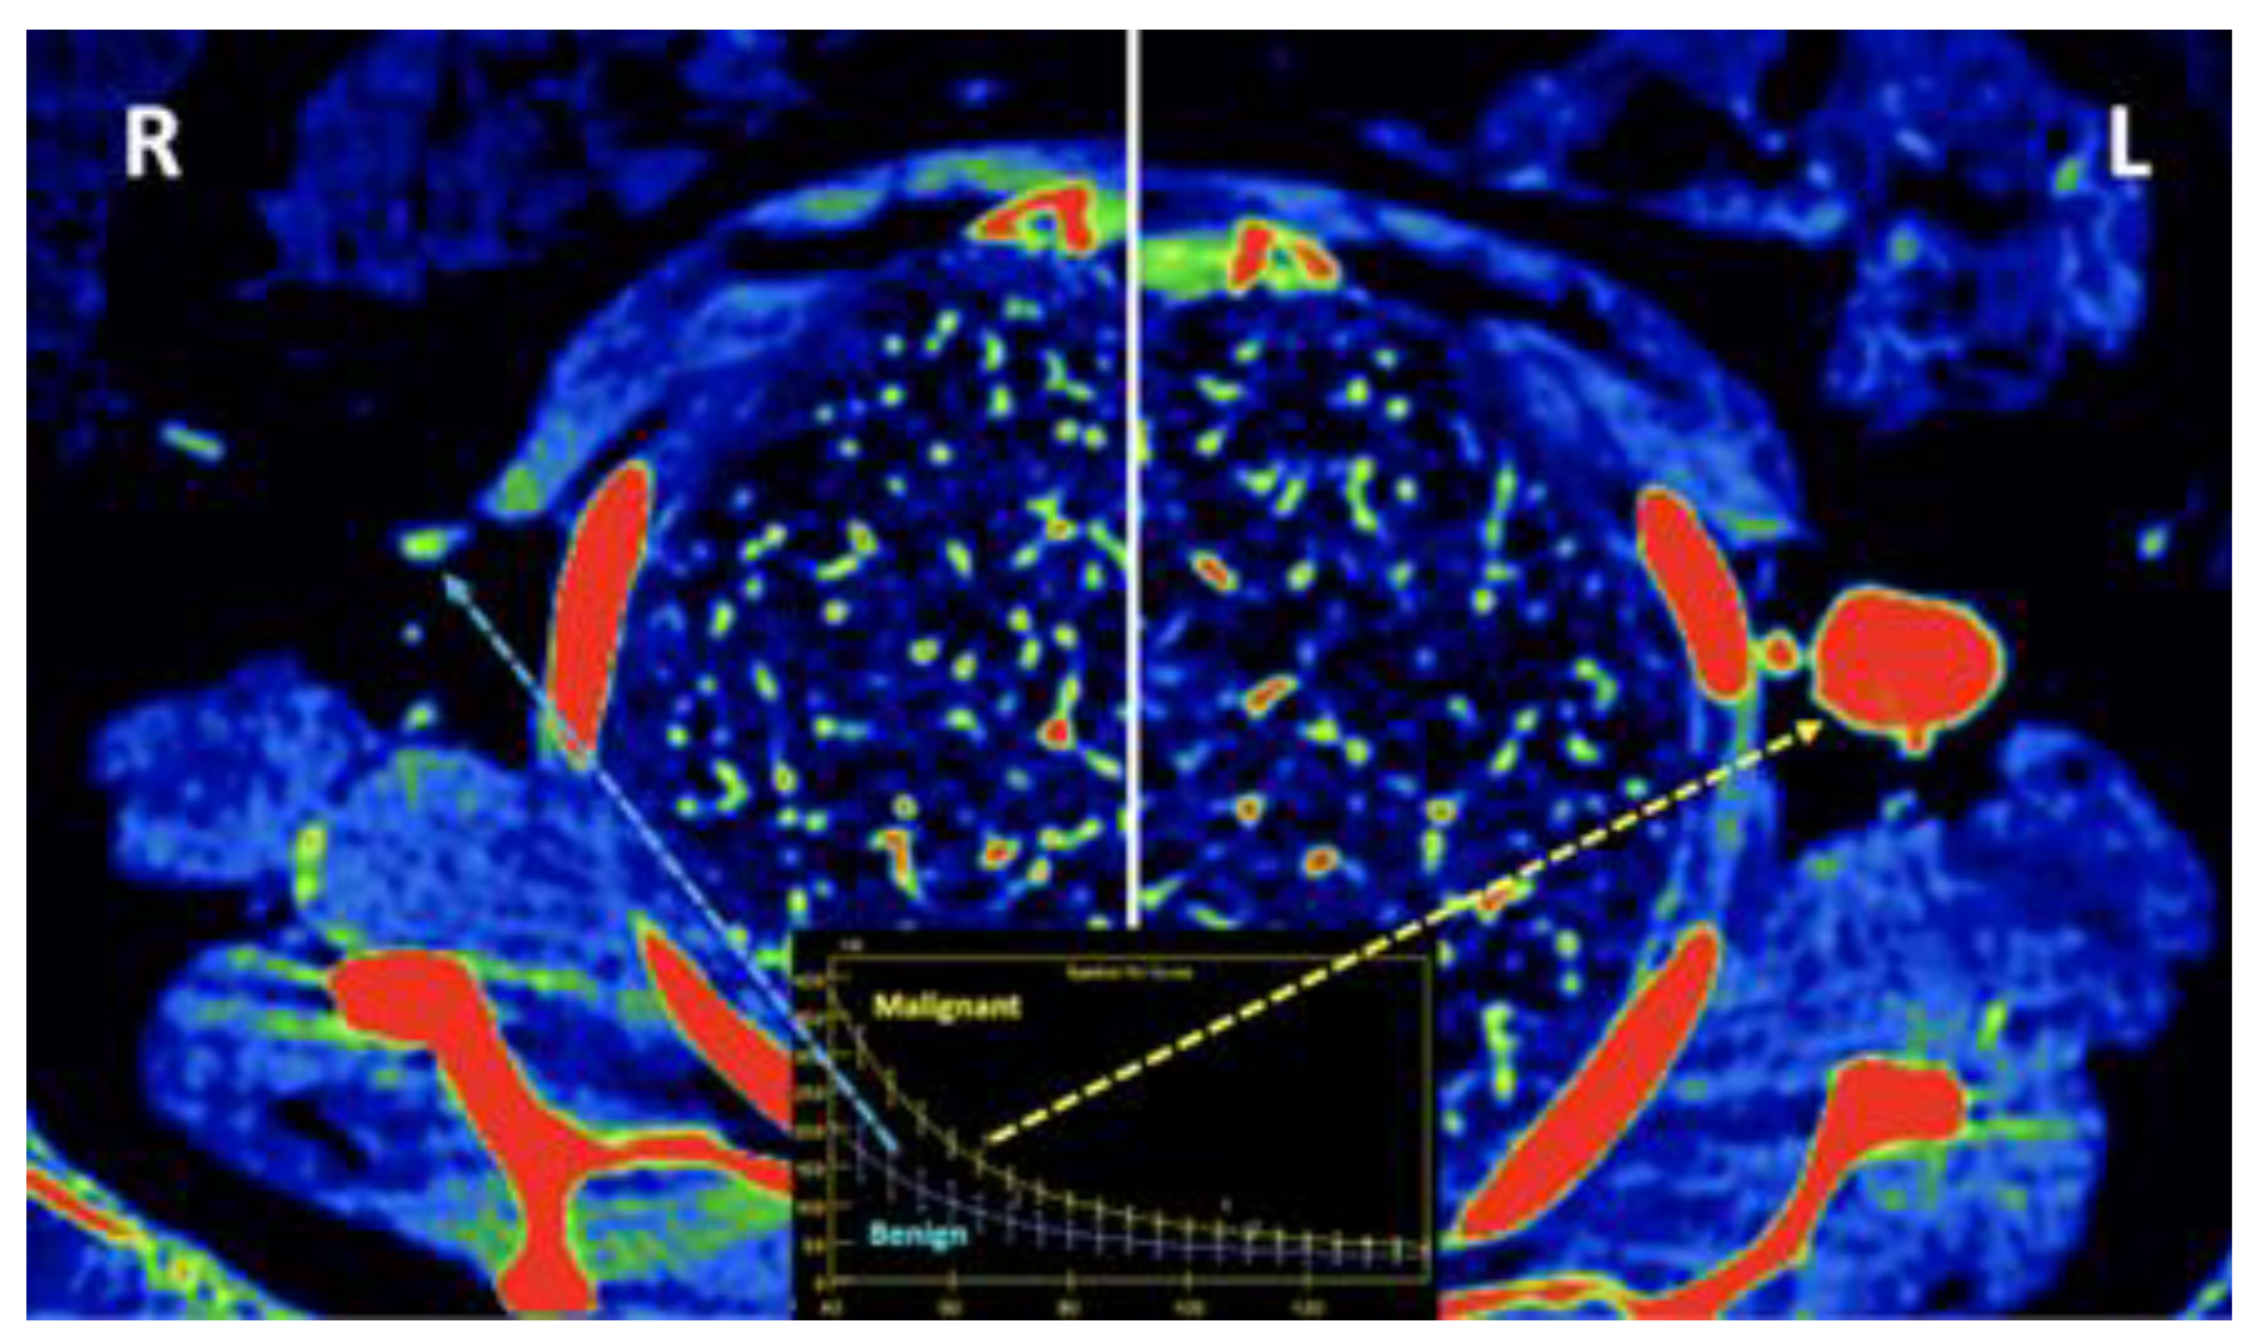

- Currently, there is not a widely reported use of DECT in clinical management of prostate cancer. However, DECT imaging may facilitate the depiction of focal areas of increased enhancement in the periphery of the prostate at contrast-enhanced CT that may represent a clinically significant cancer and deserve further workup [42] [Figure 13].